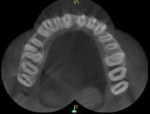

A 25-year-old male patient reported to the outpatient department with the chief complaint of pain in the left upper back region of jaw for the last 2 to 3 days. The patient also gave a history of disturbed sleep. Findings from the clinical examination revealed a deep carious lesion in the maxillary left first molar. The tooth was sensitive to percussion and elicited positive response on thermal and electric pulp testing; pain persisted even after removal of the stimulus. An intraoral periapical radiograph revealed a radiolucency approximating the pulp and periodontal ligament space widening was also present (Figure 1). On correlating the clinical and radiographic findings, a diagnosis of acute irreversible pulpitis with apical periodontitis was made and a decision to perform root canal treatment of maxillary left first molar was determined. The patient was informed about the treatment, and he provided informed consent. The patient was administered local anesthesia of 2% lidocaine containing 1:80,000 epinephrine and an access opening was performed using a rubber dam isolation. The clinical evaluation of the internal anatomy revealed 3 principal root canal systems: mesiobuccal (MB), distobuccal (DB), and palatal (P). After careful probing using a DG 16 endodontic explorer (Dentsply Sirona, dentsply.com), under 2.5X magnification using surgical loupes (Keeler Instruments, keelerusa.com), a small hemorrhagic point was noticed in a groove from the MB orifice in a palatal direction. A similar hemorrhagic point was also observed near the orifice of the main palatal canal. The conventional triangular access was modified to a trapezoidal shape to improve access to the additional canals. In both areas, there was a “catch” present with the endodontic explorer. Multiple radiographs at different angulations were not conclusive, so a multislice CBCT (Kodak, Carestream, carestreamdental.com) scan was performed of the involved tooth along with adjacent teeth. All required measures were taken to protect the patient from radiation. The images were obtained in transverse, axial, and sagittal sections of 0.5-mm thickness, which is used routinely. CBCT scan slices revealed 5 canals (2 mesiobuccal, 2 palatal, and 1 distobuccal) in the axial images at the coronal (Figure 2) and middle thirds (Figure 3). In the apical third, the palatal root had only 1 canal indicating that the 2 canals were fused between middle and apical thirds (Figure 4).